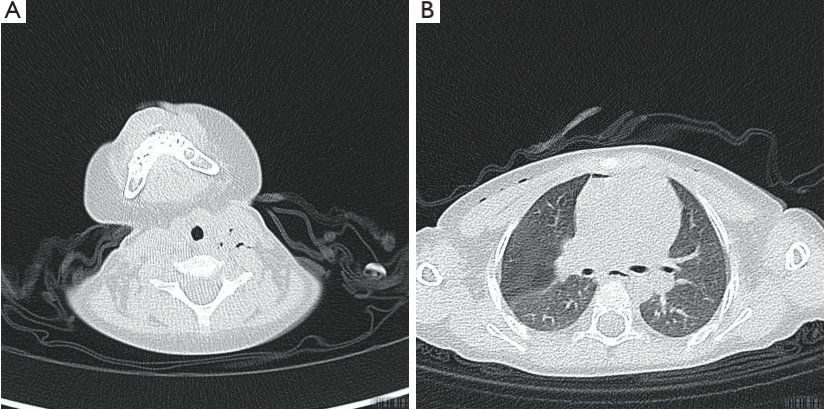

术后第2天进行的CT显示双侧气胸,右侧气胸比左侧气胸更明显,颈部和胸壁有皮下气肿,纵隔气肿,两肺有斑片状阴影(图2)。对患儿进行了紧急胸腔闭式引流,在右侧放置了一根胸管,没有任何并发症。患儿继续接受氧气进行对症治疗。

图2. CT显示双侧气胸、皮下气肿和纵隔气肿